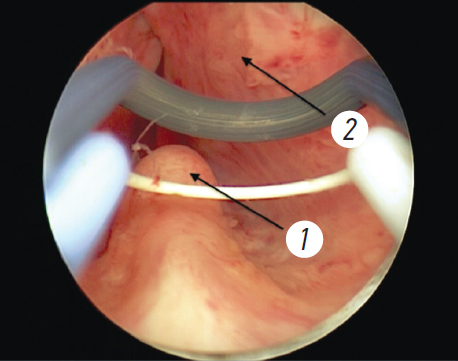

Хирургический этап лечения включал диагностическую уретроцистоскопию, позволяющую оценить состояние мочеиспускательного канала, шейки и слизистой оболочки мочевого пузыря, расположение устьев мочеточников, размеры предстательной железы (рис. 1). Следующим этапом было «вхождение в слой»: инцизия в области шейки мочевого пузыря до достижения волокон капсулы простаты с последующей энуклеацией аденоматозных узлов (рис. 2). Заключительный этап — морцелляция узлов гиперплазии. Все оперативные вмешательства проводили под спинальной анестезией.

Рис. 1. Уретроскопия при биполярной энуклеации предстательной железы. 1 — семенной бугорок, 2 — аденоматозный узел левой доли предстательной железы